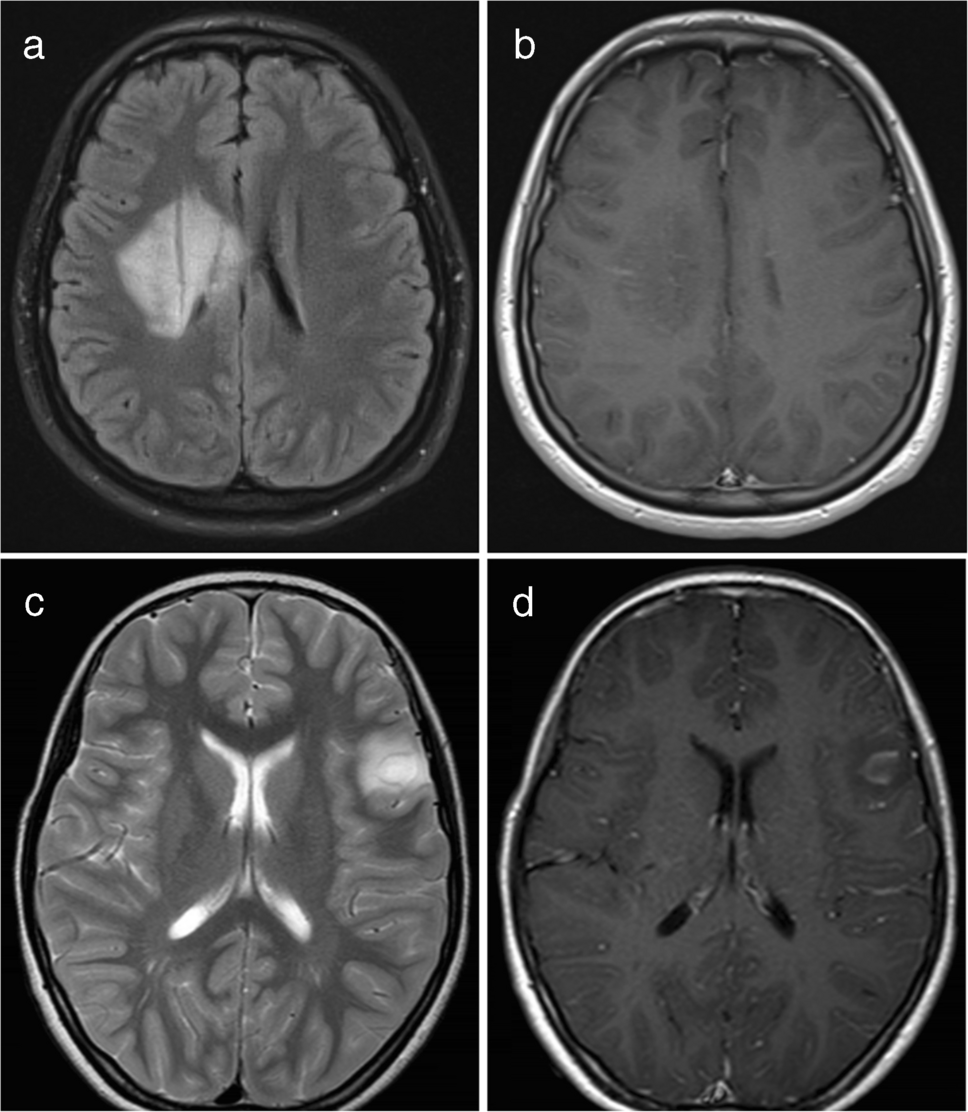

Typical ADEM on brain MRI was defined by the presence of bilateral, diffuse, poorly demarcated, large (> 1–2 cm) confluent lesions primarily affecting the cerebral white matter (Fig. 1) [23]. The following imaging features were considered atypical for ADEM [24]: unilateral lesions, well-defined lesions, exclusively small lesions (all < 2 cm), T1-hypointense lesions, lesions oriented perpendicular to the ventricles, lesions predominantly affecting the subcortical white matter more than the periventricular or deep white matter, and definite cortical involvement (Fig. 2). T1-hypointense lesions were defined as those appearing hypointense compared to gray matter on T1-weighted imaging. When evaluating lesion size, confluent lesions were regarded as large even if composed of multiple smaller aggregating lesions. Subcortical white matter lesions with suspected involvement of the adjacent cortex were not classified as cortical lesions.

Fig. 1

Typical acute disseminated encephalomyelitis (ADEM). Typical ADEM was characterized by bilateral, diffuse, poorly demarcated, large (> 1–2 cm) confluent lesions primarily affecting the cerebral white matter. a Axial fluid-attenuated inversion recovery image from a 5-year-old girl with myelin oligodendrocyte glycoprotein antibody-associated acute disseminated encephalomyelitis (MOG-ADEM) demonstrates bilateral, diffuse, large confluent white matter lesions. b Axial fluid-attenuated inversion recovery image from a 6-year-old boy with MOG-ADEM shows a similar pattern of bilateral, diffuse, confluent white matter lesions, although the margins are less distinct compared to those in (a)

Fig. 2

Representative magnetic resonance imaging features considered atypical for acute disseminated encephalomyelitis. a Axial T2-weighted image in a 5-year-old boy with myelin oligodendrocyte glycoprotein antibody-associated acute disseminated encephalomyelitis (MOG-ADEM) shows well-demarcated lesions predominantly involving subcortical white matter. b Axial fluid-attenuated inversion recovery image in a 5-year-old girl with MOG-ADEM shows small (< 2 cm) lesions. c Axial T1-weighted image in an 11-year-old girl with MOG-ADEM shows a T1-hypointense lesion (arrow) compared to gray matter. d Axial T2-weighted image in a 2-year-old girl with MOG-ADEM shows white matter lesions oriented perpendicular to the ventricles (arrows), appearing as laterally extending striations. e, f Axial T2-weighted (e) and fluid-attenuated inversion recovery (f) images in a 3-year-old boy with MOG-ADEM show cortical lesions (arrows)